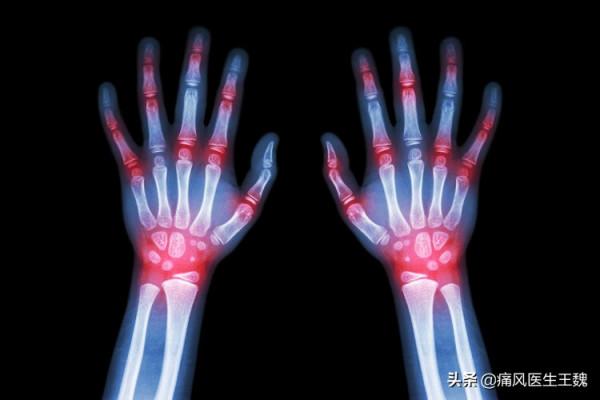

痛風的好發部位是下肢關節,關節區域性會出現紅腫、發熱等表現,一部分患者特別是首次發作的患者會誤以為扭傷、關節勞損等,會採用熱敷、泡腳等措施。

急性痛風性關節炎好發於足部,關節處會出現充血、水腫,將足部適當抬高,能減輕水腫,有助於緩解疼痛。